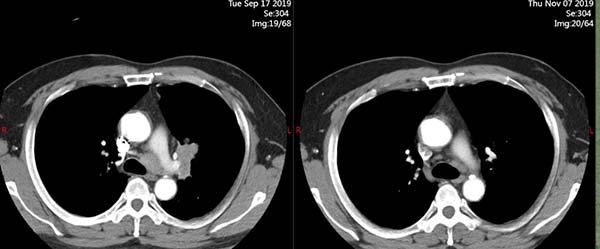

治疗前(2019.9.17)

治疗2周期后(2019.11.07)

在完成2个周期的治疗后,病灶显著缩小!时间是最好的试金石。一个月,两个月,一年,两年……至今,四年过去了。李某的病情得到了持续而深度的缓解,他定期返院复查,生活几乎恢复了正常。他可以重新陪伴孩子成长,可以陪着妻子散步,可以承担起家庭的责任。这四年,对他而言,是失而复得的黄金四年。